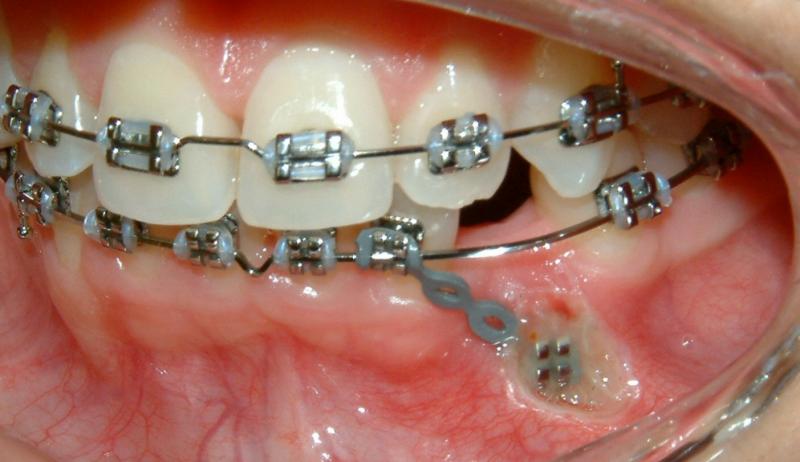

In the 2nd post-op visit (2 weeks after the surgery), the pulling is activated. The force exerted in pulling can be estimated from the shape of the hole of the color tie (Fig. 21). It deforms from a perfect circle (unstretched) to an approximated ellipse (stretched); shown by the blue arrow. The figure also shows improved healing.

Fig. 21 Second post-op visit, 2 weeks after surgical exposure; activated pulling (progress, improved healing)© Copyright 2007-2014, Vu Orthodontics. All rights reserved.

In the 3rd post-op visit (2 months after the surgery), the pulling is again activated. The progress of tooth movement can be seen, comparing the lengths of the elastic elements in Figs. 21 & 22. The newly-formed healthy gingiva can also be seen around the bracket that is attached to the crown of the lower left canine (Fig. 22).

Fig. 22 Third post-op visit, 2 months after surgical exposure; activated pulling (progress, complete healing)

© Copyright 2007-2014, Vu Orthodontics. All rights reserved.

In the 4th post-op visit (3 months after the surgery), the forced-eruption is again activated. This time is by using a piggyback mechanics. The progress of tooth eruption is shown in Fig. 23. Note that the crown of the tooth (lower left canine) is surrounded by healthy gingiva.

Fig. 23 Fourth post-op visit, 3 months after surgical exposure; activated forced eruption (progress)